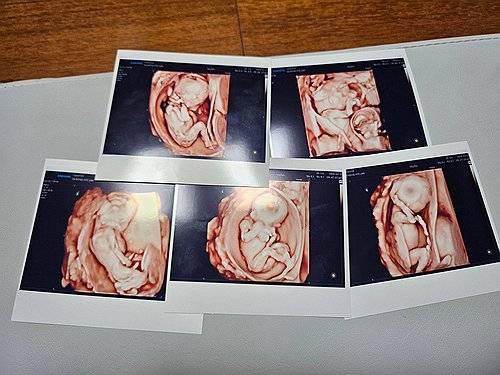

"아기집이 5개 생긴 것을 보고 첫 2주 동안은 우리 부부 둘 다 매일 울었어요." 자연임신으로 생긴 다섯쌍둥이로 '오둥이' 아빠가 된 김준영(31)씨는 22일 연합뉴스에 처음 다섯쌍둥이를 확인한 날을 떠올리며 이같이 말했다.

임신 준비에 오래 걸린 편은 아니어서 다행스러웠지만, 이들 부부 역시 한 번에 다섯명의 아기가 생길 줄은 상상조차 하지 못했다. 임신 사실을 확인한 것은 뱃속 아기들이 5∼6주 차쯤 됐을 무렵인 4월께였다. 김씨는 아기집 5개를 확인했을 당시 심정을 묻는 말에 당황스러운 웃음을 지었다.

그는 "교직에 있으니 아이들을 좋아하고, 자녀 계획을 세우는 데 영향이 있긴 했다"면서도 "자녀 한두명을 생각했었는데 다섯을 가질 줄은 몰랐다"고 말했다. 그러면서 "(아기집을 보고) 첫 2주간 둘이서 맨날 울었다"며 "다섯쌍둥이가 생겼다는 사실을 받아들이기 힘들었다"고 말했다.